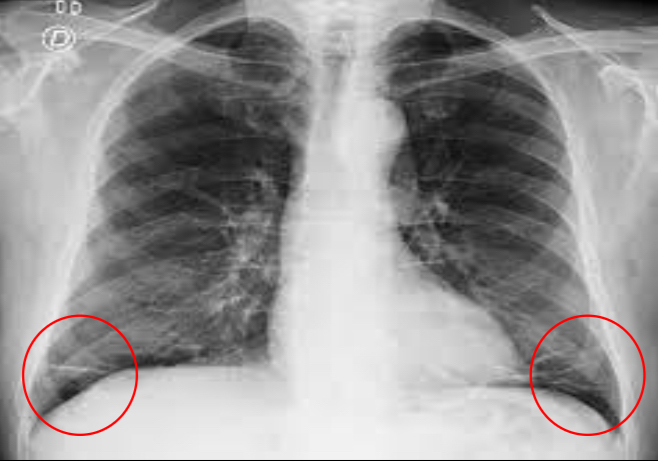

¿Qué patrón es el siguiente?

atelectasia

31

causas de una atelectasia

- obstrucción de un bronquio - compresión externa por derrame pleural - contracción por fibrosis pulmonar - heridas de arma

32

morfología de una atelectasia

triangular con base hacia la pleura y vértice hacia íleo o morfología lineal, ocasionando una retracción de estructuras

¿Qué patrón puedes ver?

atelectasia de morfología líneal